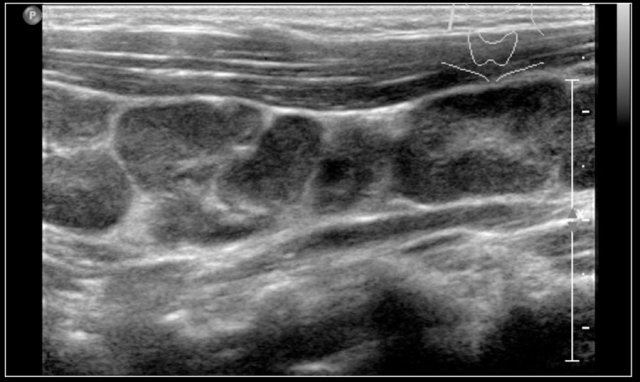

The ultrasound shows several enlarged hypoechoic lymhnodes, that lack an hyper-echoic hilum.

Here another fourteen-year-old boy with a painless swelling in the left neck.

Ultrasound showed several enlarged lymhnodes.